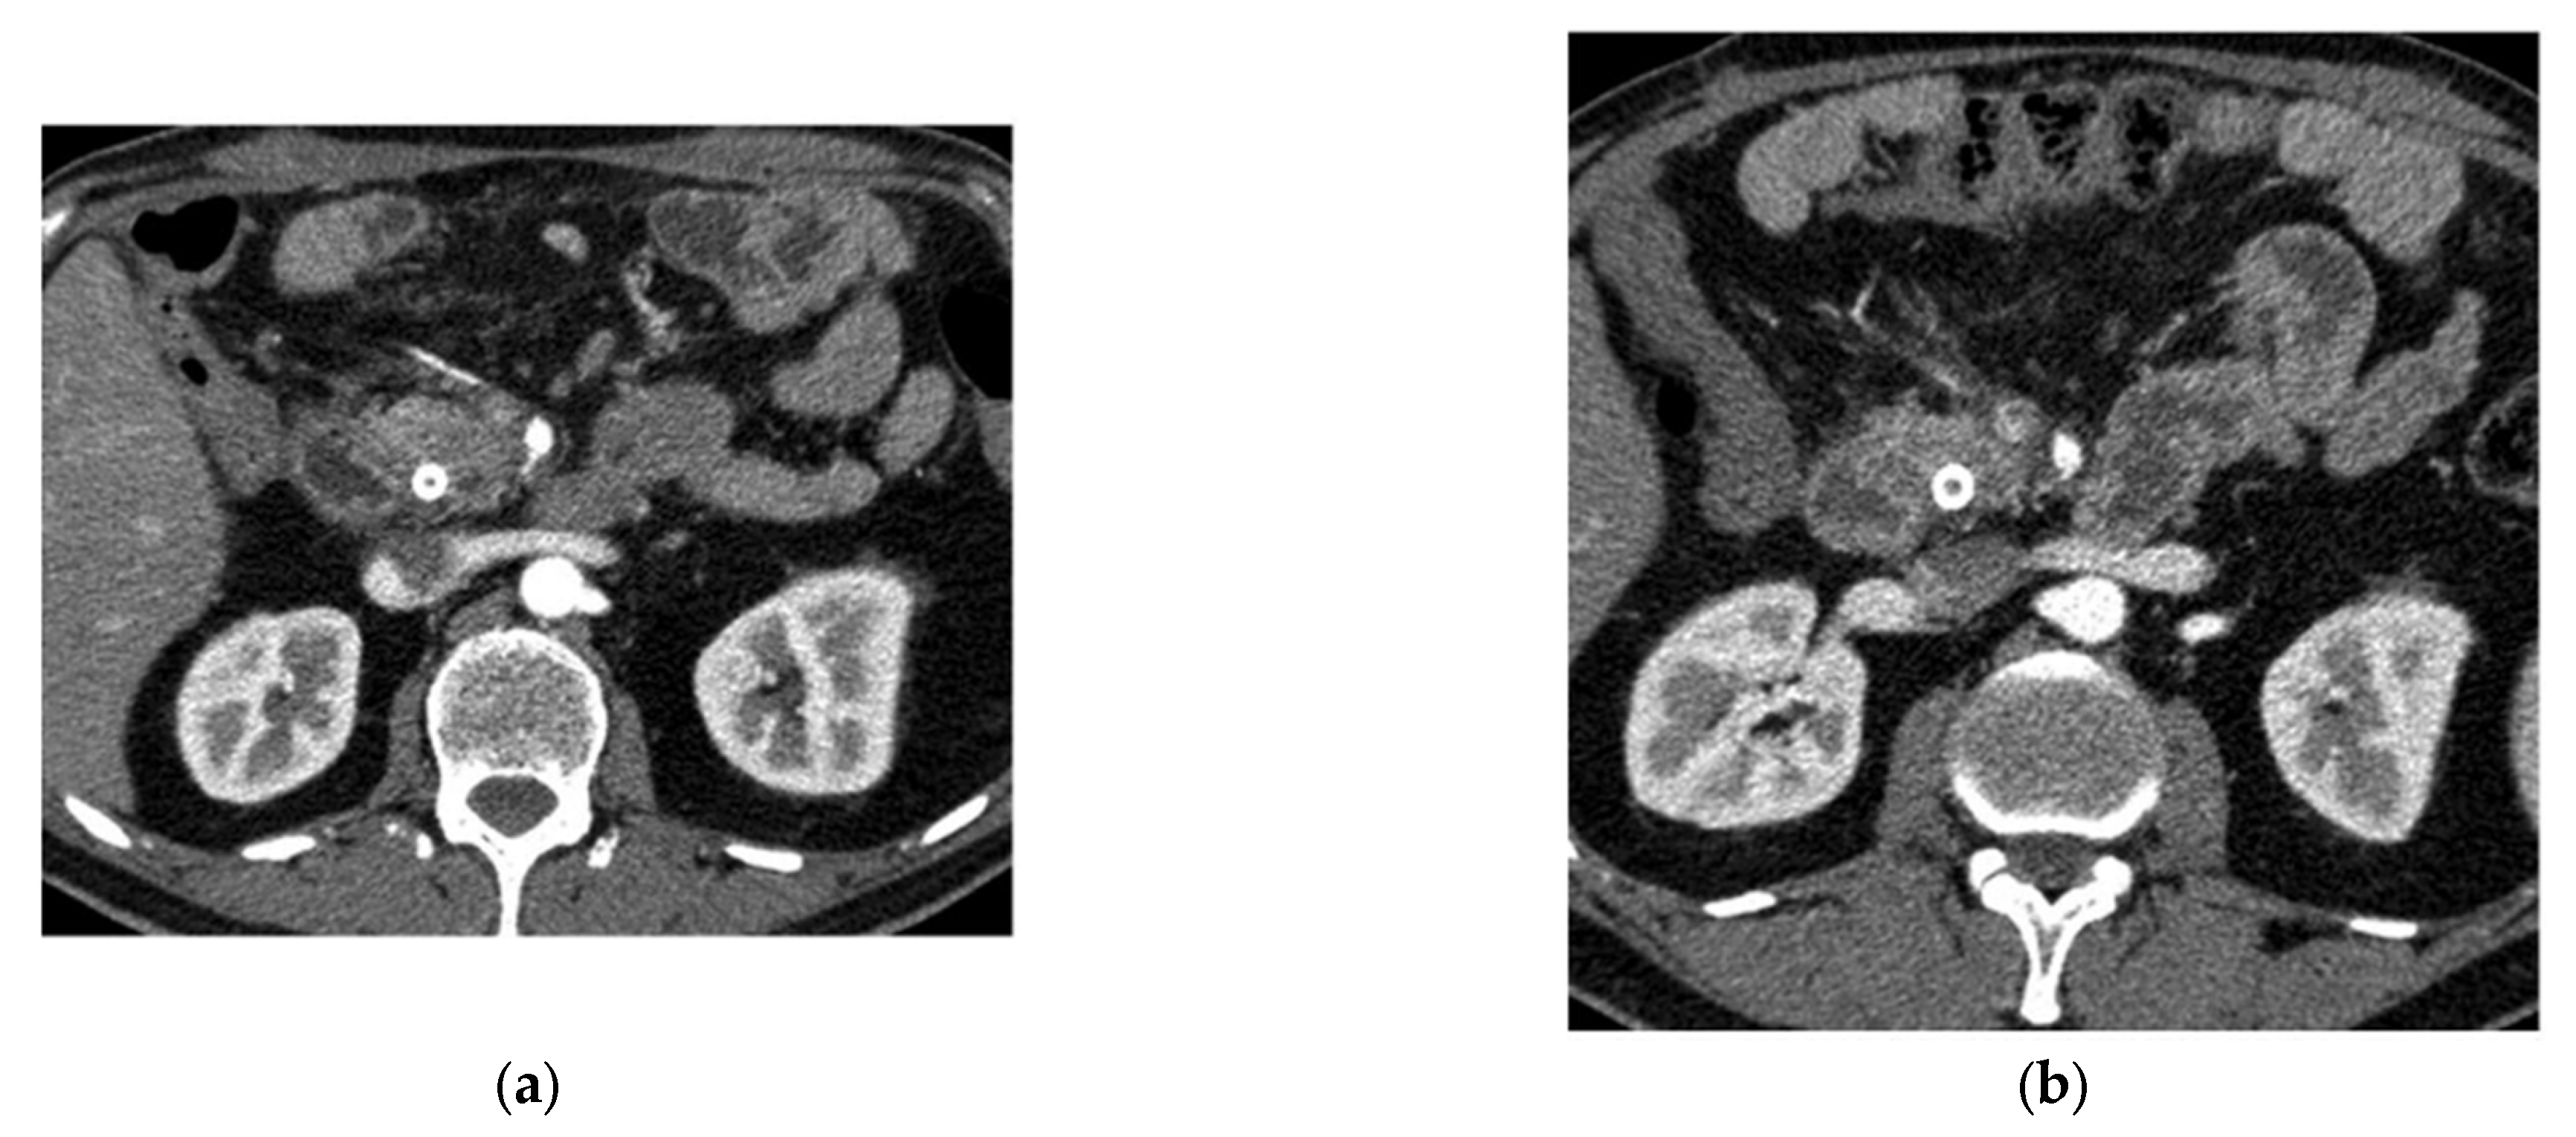

- Mukherjee, S.; Patra, A.; Khasawneh, H.; Korfiatis, P.; Rajamohan, N.; Suman, G.; Majumder, S.; Panda, A.; Johnson, M.P.; Larson, N.B.; et al. Radiomics-Based Machine-Learning Models Can Detect Pancreatic Cancer on Prediagnostic Computed Tomography Scans at a Substantial Lead Time Before Clinical Diagnosis. Gastroenterology 2022, 163, 1435–1446.e3. [Google Scholar] [CrossRef]

- Chen, W.; Zhou, Y.; Asadpour, V.; Parker, R.A.; Puttock, E.J.; Lustigova, E.; Wu, B.U. Quantitative Radiomic Features From Computed Tomography Can Predict Pancreatic Cancer up to 36 Months Before Diagnosis. Clin. Transl. Gastroenterol. 2023, 14, e00548. [Google Scholar] [CrossRef]